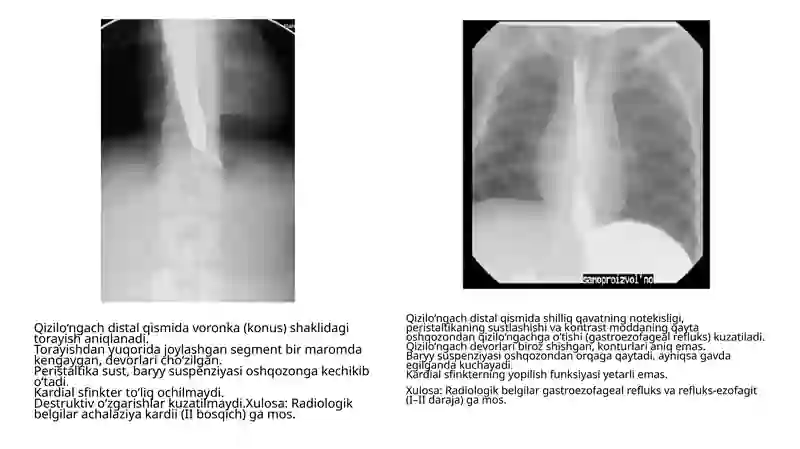

Rentgen tahlillari yig'indisi tibbiy radiologiya